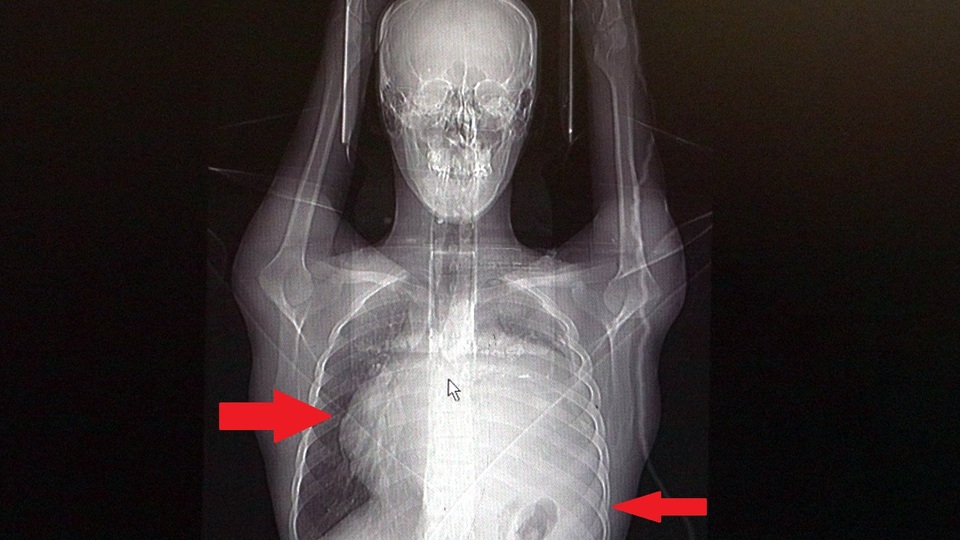

İstanbul´da yaşayan 21 yaşındaki Burak Aktaş, Temmuz ayında işe girmek üzere sağlık raporu almak için hastaneye gitti. Herşey yolundaydı ve raporunu alarak iş başı yaptı. Bir ay geçmeden nefes darlığı, halsizlik, öksürük gibi şikayetlerle başka bir hastaneye gittiğinde ise ilk şoku yaşadı. Sol göğüs boşluğunda portakal büyüklüğünde bir kitle tespit edilmişti. Yapılan biyopside tümörün akciğer kaynaklı olmadığı, henüz cenin aşamasında eşey hücrelerinin farklılaşmasıyla gelişen "immatür teratom" teşhisi kondu. Kitleyi küçültmek için kemoterapi uygulansa da tam tersine tümör 2 ay içinde neredeyse 10 katına çıktı ve büyük bir karpuz boyutuna ulaştı. Sol akciğerinin yüzde seksenini kağıt gibi ezen, kalbini göğüs duvarında 12 santim sağa kaydıran ve hem kalbe hem beyne giden ana damarlara baskı yapan 6.5 kilo ağırlığındaki dev tümör, Koşuyolu Yüksek İhtisas Eğitim ve Araştırma Hastanesi Göğüs ve Kalp Damar Cerrahisi ekiplerinin birlikte girdiği operasyonla başarılı şekilde çıkarıldı. Operasyon sırasında Aktaş´ın kalbi normal yerine çekildi, sol akciğerin üst lobu alındı, ezilen alt lobu ise anestezi ekipleri tarafından pozitif basınçla yeniden şişirildi. Ameliyatı gerçekleştiren ekipten Prof. Dr. Erdal Taşçı, Aktaş´ın göğüs boşluğunun neredeyse tamamını kaplayan 6,5 kiloluk tümörün teratom (eski Yunancada `canavar tümör´) türlerinden biri olduğunu ve embriyonik hücrelerden kaynaklandığını kaydetti.

Prof. Dr. Erdal Taşçı, "Bundan 2,5-3 ay öncesine kadar hiçbir problemi olmayan, hayatını normal devam ettiren bir delikanlı Burak. Göğüs ağrısı öksürük ve nefes darlığı şikayetiyle sağlık kuruluşuna başvuruyor. Orada yapılan tetkiklerinde sol göğüs boşluğunda akciğerinden kaynaklanmayan portakal büyüklüğünde bir kitle tespit ediliyor ve immatür teratom tanısı konuyor. 2 ay arayla yapılan tetkiklerinde ve arada cerrahi öncesi küçültme amaçlı kemoterapi almasına rağmen, portakal büyüklüğündeki tümör, irice bir karpuz büyüklüğüne, yaklaşık 6 kilo 300 grama kadar ulaşıyor. Göğüs boşluğunda kemik kafesi içinde olduğu için, itebileceği iki organ var; biri kalp, diğeri de akciğerler. Soldan sağa doğru büyüdüğü için kalbi tamamen göğüs boşluğunun sağ tarafına itmiş ve kalbe giren ve kalpten çıkan bütün büyük damarları da yer değiştirmenin etkisiyle bükülmüş durumdaydı. Bu nedenle vücuduna yeterince kan gitmiyordu. Ağustos ayının başında portakal büyüklüğündeyken kitle Eylül sonuna irice bir kavun, Ekim ayına geldiğimizde ise bir karpuz büyüklüğüne ulaştığı için, kitlenin büyüme hızı bizi acilen ameliyat yapmaya yöneltti. Yaklaşık 8-10 kat hacimsel olarak artmıştı. Sol akciğer tamamen ezilmiş ve kağıt haldeydi, alt lobu anestezi ekibimiz yüksek basınç uygulayarak tekrar şişirdi. Çok fazla vaktimiz yoktu, kitle basısından dolayı yaşamla bağdaşmayacağından dolayı hızlı hareket etmek zorundaydık. Bize geldikten üç gün sonra hemen ameliyata aldık çünkü tümörden ziyade onun yaptığı baskıdan kaynaklı hayati riski vardı" dedi.

Normalde kalbin özellikle alt ucunun göğüs boşluğunda, iman tahtası orta çizgi kabul edilirse, sola bakar şekilde durduğuna dikkat çeken Prof. Dr. Taşçı, sözlerini şöyle sürdürdü: "Ama bu hastada yaklaşık 12-13 s santimlik kalbin alt ucununu yer değiştirmesi ve kalbe giren çıkan bütün damarlar bükülüp kan akımı bozulmuştu. Kalp Damar Cerrahisi ekibi de bizimle beraber ameliyata girdi. Sol akciğerin üst lobu artık geri dönüşümsüz olarak ezildiği için çıkarmak zorunda kaldık. Kalbi tekrar eski pozisyonuna getirdik. Ameliyat sonrası çok çabuk toparladı. Koşuyolu ailesi olarak böyle büyük bir vakanın altından başarıyla çıktığımız için de ayrıca çok gururluyuz. Bundan sonra onkolog arkadaşlarımız hastamızın yaşamına çok olumlu dokunuşlar yapacak. İmmatür teratom genelde embriyojenik çağda gelişim gösteren germ hücrelerinin farklılaşmasıyla büyür. Vücudun herhangi bir yerinde gelişebilir ve içinde saç, diş, kemik artıkları, jölemsi kıvamda maddeler bulundurabilen bir tümör çeşididir. Kombine tedavilerde çok iyi sonuçlar alınıyor. Bu çocuğumuzu ileride güzel bir hayat bekliyor."